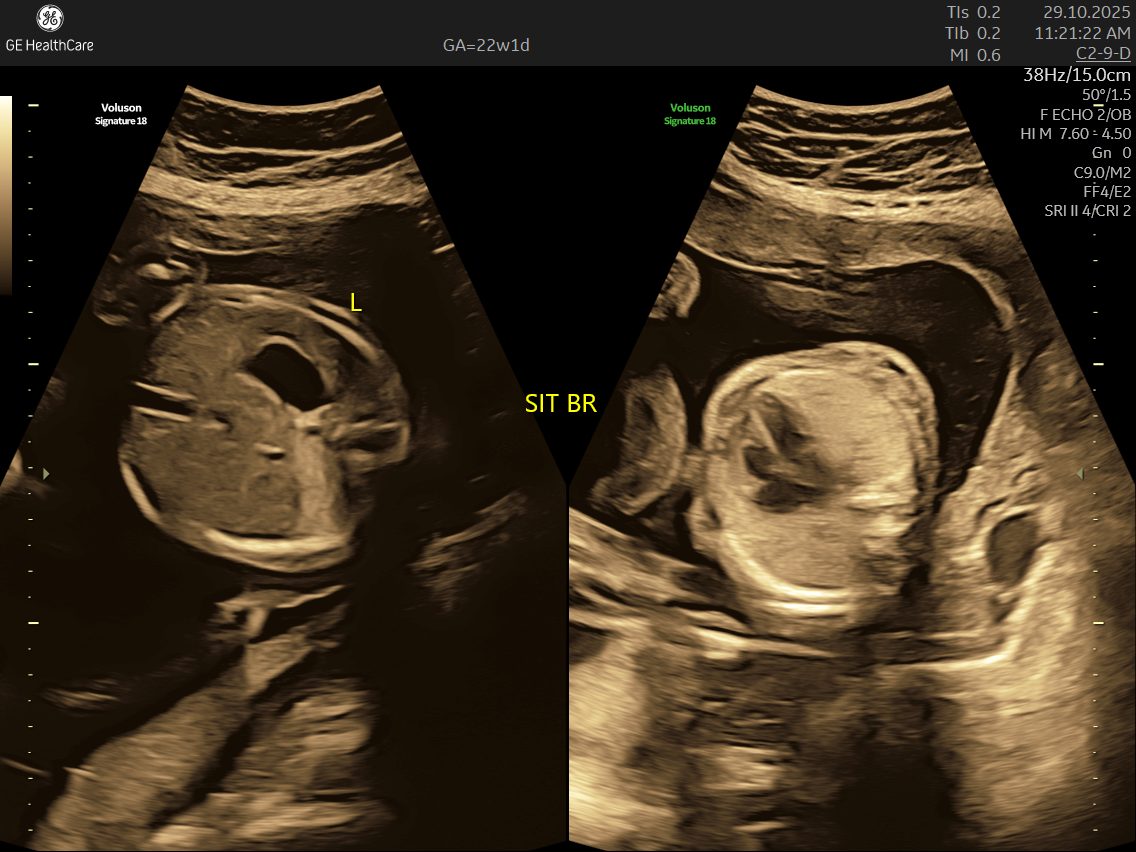

Fetal echocardiography is a valuabe early screening tool for Fetal Heart Defects. It is a specialized ultrasound scan that closely examines your baby’s heart while still in the womb. Unlike standard pregnancy scans, this test focuses on evaluating the structure, function, and rhythm of the fetal heart—providing incredibly detailed insights that help detect and diagnose congenital heart defects (CHDs) and other abnormalities early.

- Focus on the Heart: This scan is dedicated solely to assessing your baby’s heart—its structure, blood flow, and rhythm—offering a far deeper evaluation than standard ultrasounds.

- High Detail: Utilizing advanced Doppler ultrasound technology, it tracks blood movement through the heart and valves, highlighting issues that general scans often cannot detect.

- Specialized Equipment and Expertise: Performed with high-resolution machines and by specialist doctors, fetal echocardiography pinpoints tiny structural or functional abnormalities that conventional scans may miss—helping ensure early, accurate diagnosis and informed planning.

- Using the advanced GE Voluson S10 ultrasound machine—renowned for its superior imaging clarity, 4D real-time visualization, and automated analysis tools that significantly increase diagnostic accuracy and reduce the chances of missing subtle heart defects.

- Its a specialized ultrasound done between 18–24 weeks of Gestational Age that evaluates the structure, function, and rhythm of a baby’s heart while still in the womb. This scan uses high-frequency sound waves to create detailed images of the fetal heart, aiding in the detection of congenital heart defects (CHDs) and other abnormalities.